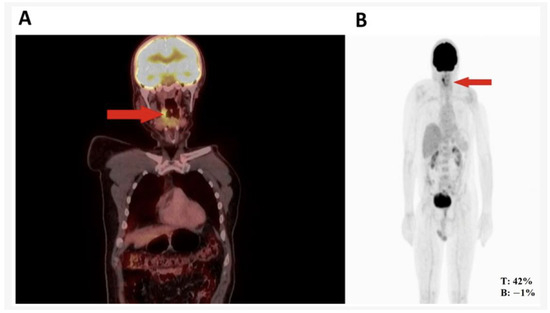

| Diagnostic aids | MRI of face and neck with contrast showing irregular enhancement measuring approximately 25 × 25 × 16 mm in pharyngeal mucosal space involving right palatine tonsil and base of tongue | PET CT * showing hypermetabolic nodule of right pharynx and palatoglossal arch measuring 22 × 10 mm | Endoscopy: moderate, active, non-atrophic chronic gastritis; no malignant neoplasia; Entero-MRI: distended stomach with compact image inside, nonspecific thickening of jejunal loops; contrast-enhanced abdominal CT |